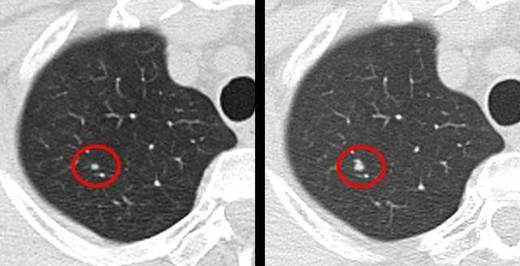

班长课堂031 | 肺部结节10.5mm医案一则

肺部结节10.5mm医案一则